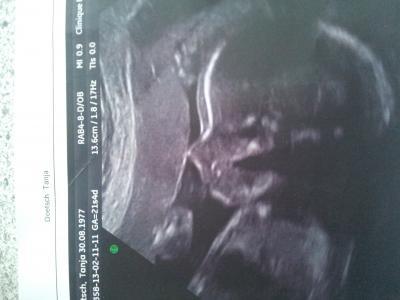

Hallo, War gestern bei der FD! Baby geht's gut. 400 g und 25 cm, Plazenta liegt gut! Wir sind happy und schwer verliebt! Also zuruecklehnen und gemuetlich weiterkugeln ! Anbei ein Bild meines Junikaeferchen, Troulli

Bild zu FD gehabt und Foto - Forum für Juni - Mamis